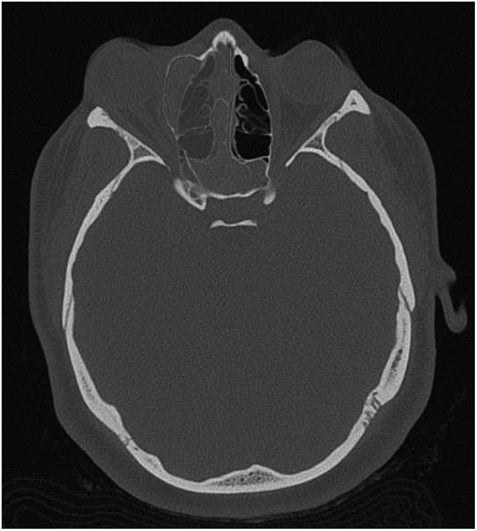

The results of the CT indicated complete opacification of the frontal, ethmoidal, sphenoidal and maxillary sinus on the right side with hyper-dense intraluminal soft tissue filling the sinus cavities. Significant widening of the ostiomeatal complex was observed (Fig. 1). Soft tissue from the right maxillary sinus extended into the right side of the nasal cavity. Extensive changes in the right ethmoidal labyrinth were also discovered. The intact lamella of the middle turbinate and lamella of the bulla ethmoidalis extended further laterally when compared to the left side, and lamina papyracea was protruding into the orbit (Figs 1 and 2). Options were discussed and endoscopic CT guided surgery was recommended.

Coronal CT image indicating extent of soft tissue in the right nasal passage, malformation of the right lamina papyracea, and complete opacification of the right maxillary, ethmoidal and frontal sinus.

Axial CT image indicating widening of the ostiomeatal complex with malformation of the right ethmoid.

Axial CT view of the ethmoid labyrinth with the left side super imposed on the right side over the midline for comparison.